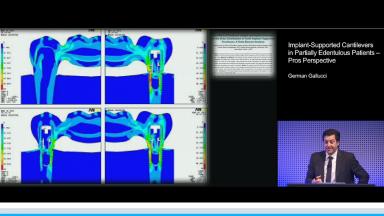

Implant-Supported Cantilevers in Partially Edentulous Patients – Pros Perspective

This lecture considers the incorporation of cantilever extensions into implant-supported prostheses as a viable option in situations where local conditions of the residual edentulous ridge preclude the possibility of placing an implant. The literature presented in this lecture substantially supports the conclusion that the incorporation of single cantilevers into implant-supported prostheses does not have a significant effect on the amount of peri-implant marginal bone loss. Literature also suggests that implant-supported fixed prostheses with crown-to-implant ratios greater than 1:2 do not correlate positively with marginal bone loss. This presentation also discusses fixed implant rehabilitations with multiple cantilevers in edentulous patients, showing that implant number and distribution along the edentulous ridge seem to influence the prosthodontic survival rates only in the maxilla.